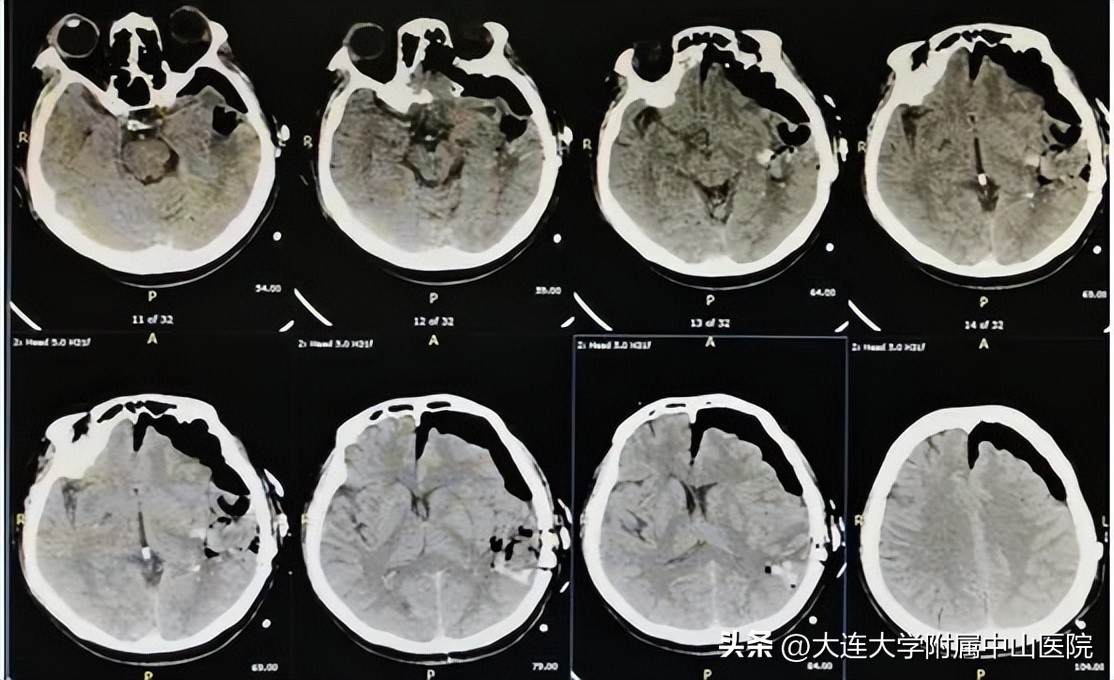

术后CT

相关工作准备就绪,手术开始。神经外二科杨秀宝医生凭借精湛的技术,在微创小切口一次性内镜扩张导管下清除患者脑内血肿,1小时的“抽丝剥茧”,清除血肿40ml左右,功能区脑组织未受破坏及骚扰,术后脑搏动良好。术后2小时患者拔除气管插管,神志转清,就可进行简单问答了,术后一天,患者问答自如,右侧肢体肌力恢复,目前已顺利出院。